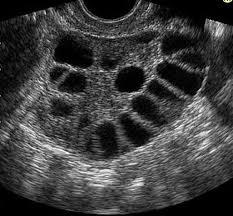

What are the USS findings for PCOS?

At least 12 cysts in one ovary measuring 2-9mm